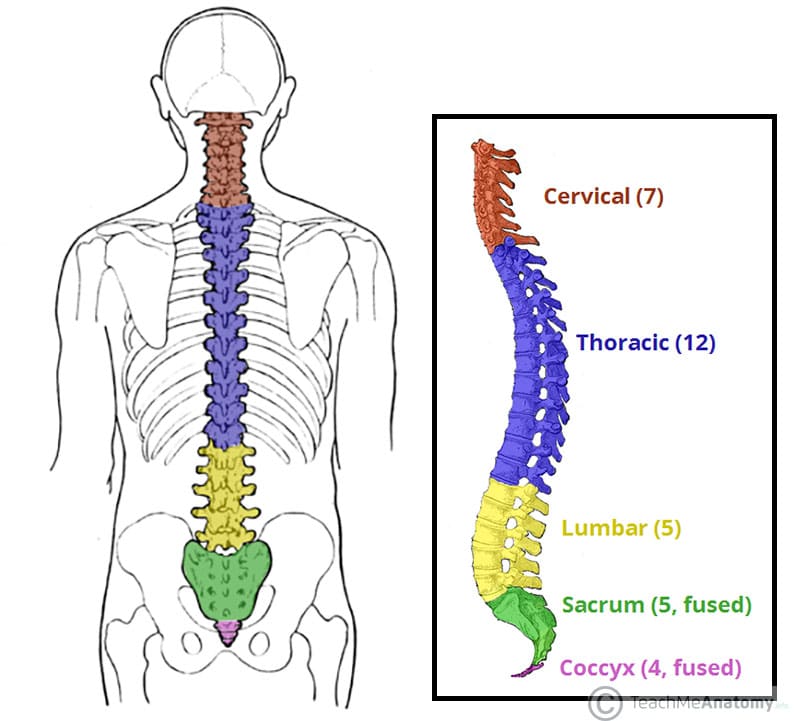

vertebral column

7 cervical vertebrae (neck)

12 thoracic vertebrae (chest)

5 lumber vertebrae (lower back)

1 sacrum = 5 fused vertebrae (midline region of buttocks)

1 coccyx = 3 or 4 fused vertebrae (tail bone)